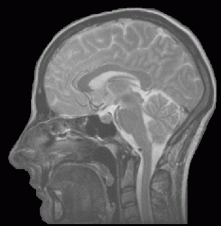

My MRIs show a spinal cord that is shedding its myelin sheath protecting the nerves inside, a couple vertebrae that have spontaneously fused—”When did you have this happen?” Dr. K asked me. “I don’t know,” I replied. “I’ve never had anything done on my back.” “Car accident?” “No.” “Okay, you have a spontaneous fusion”—and places where the nerves themselves are atrophying, withering. But my brain, my cerebellum specifically, it is a healthy brain. I have a fine-looking thinker. Thus, Dr. K posited, I do not have a spinocereballar ataxia, as my cerebellum is healthy.